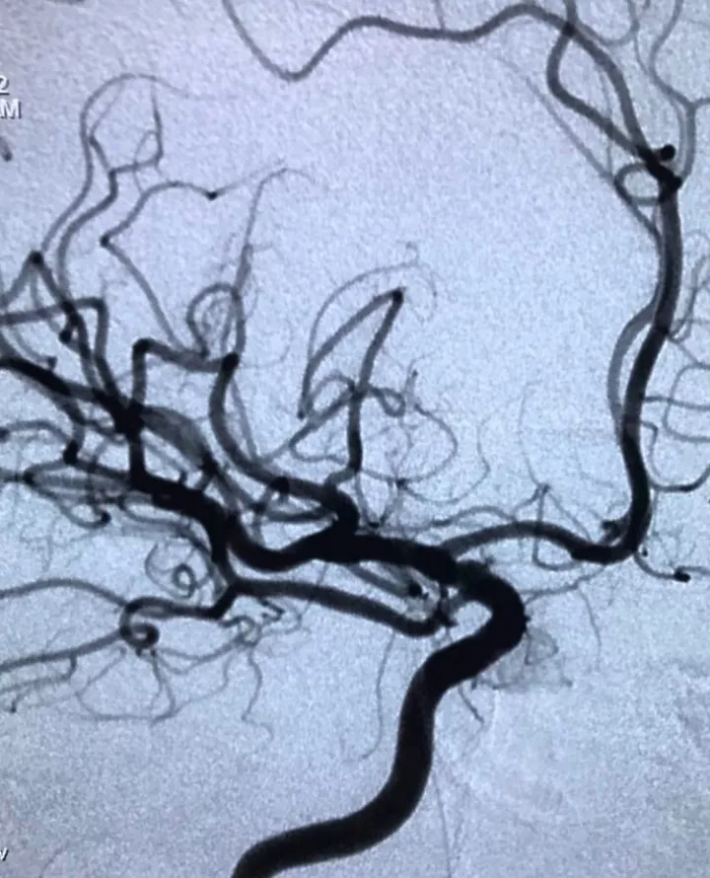

电凝2min后造影,瘤消失

撤出微导丝再造影,瘤仍不显影